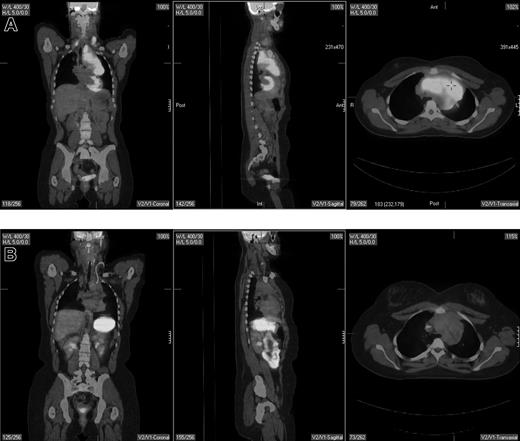

Should PET be used for restaging of lymphoma?

Pretherapy and posttherapy fused PET/CT images in a 17-year-old female patient with nodular sclerosis Hodgkin disease. The pretherapy images (top) showed bilateral supraclavicular, anterior mediastinal, and left hilar lymphadenopathy by both PET and CT. Posttherapy PET/CT performed 4 weeks following completion of 6 cycles of ABVD (doxorubicin, bleomycin, vinblastine, dacarbazine) showed resolution of disease in the supraclavicular and left hilar region but continued to show a residual 6.2 × 3.4-cm mass in the anterior mediastinum that was PET negative. Multiple biopsies of the mass showed only fibrous tissue with no evidence of lymphoma. The patient is currently without evidence of disease after 4 years of follow-up.